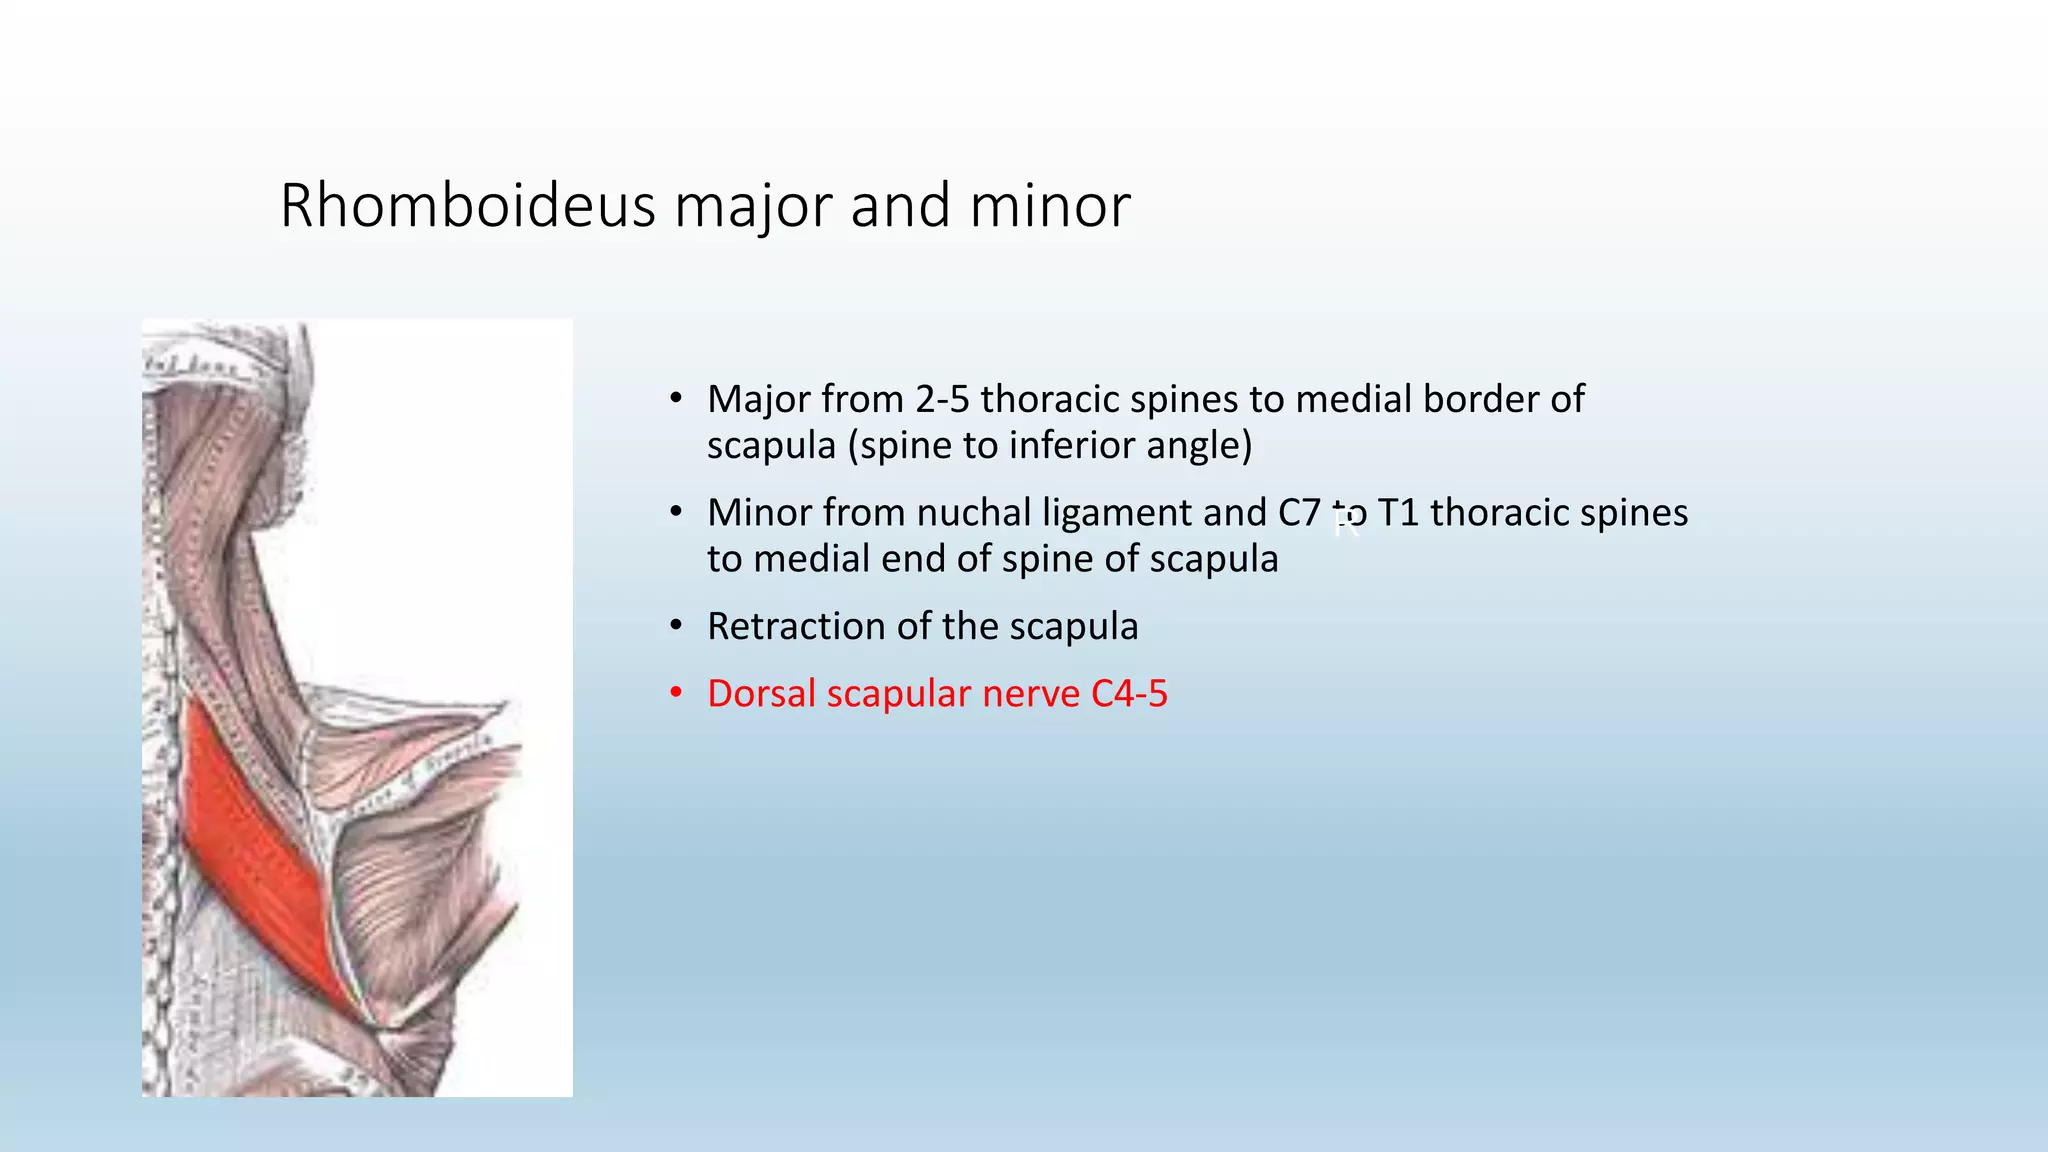

The document summarizes an anatomy revision session on the upper limb. It discusses various muscles of the upper limb including their origins, insertions, innervations and functions. Key muscles covered include the pectoralis major and minor, serratus anterior, deltoid, biceps brachii, brachialis, coracobrachialis, and triceps. It also discusses the rotator cuff muscles and muscles of the forearm including flexor carpi ulnaris and radialis. The session aims to help students identify upper limb muscles and understand their relations to nerves.